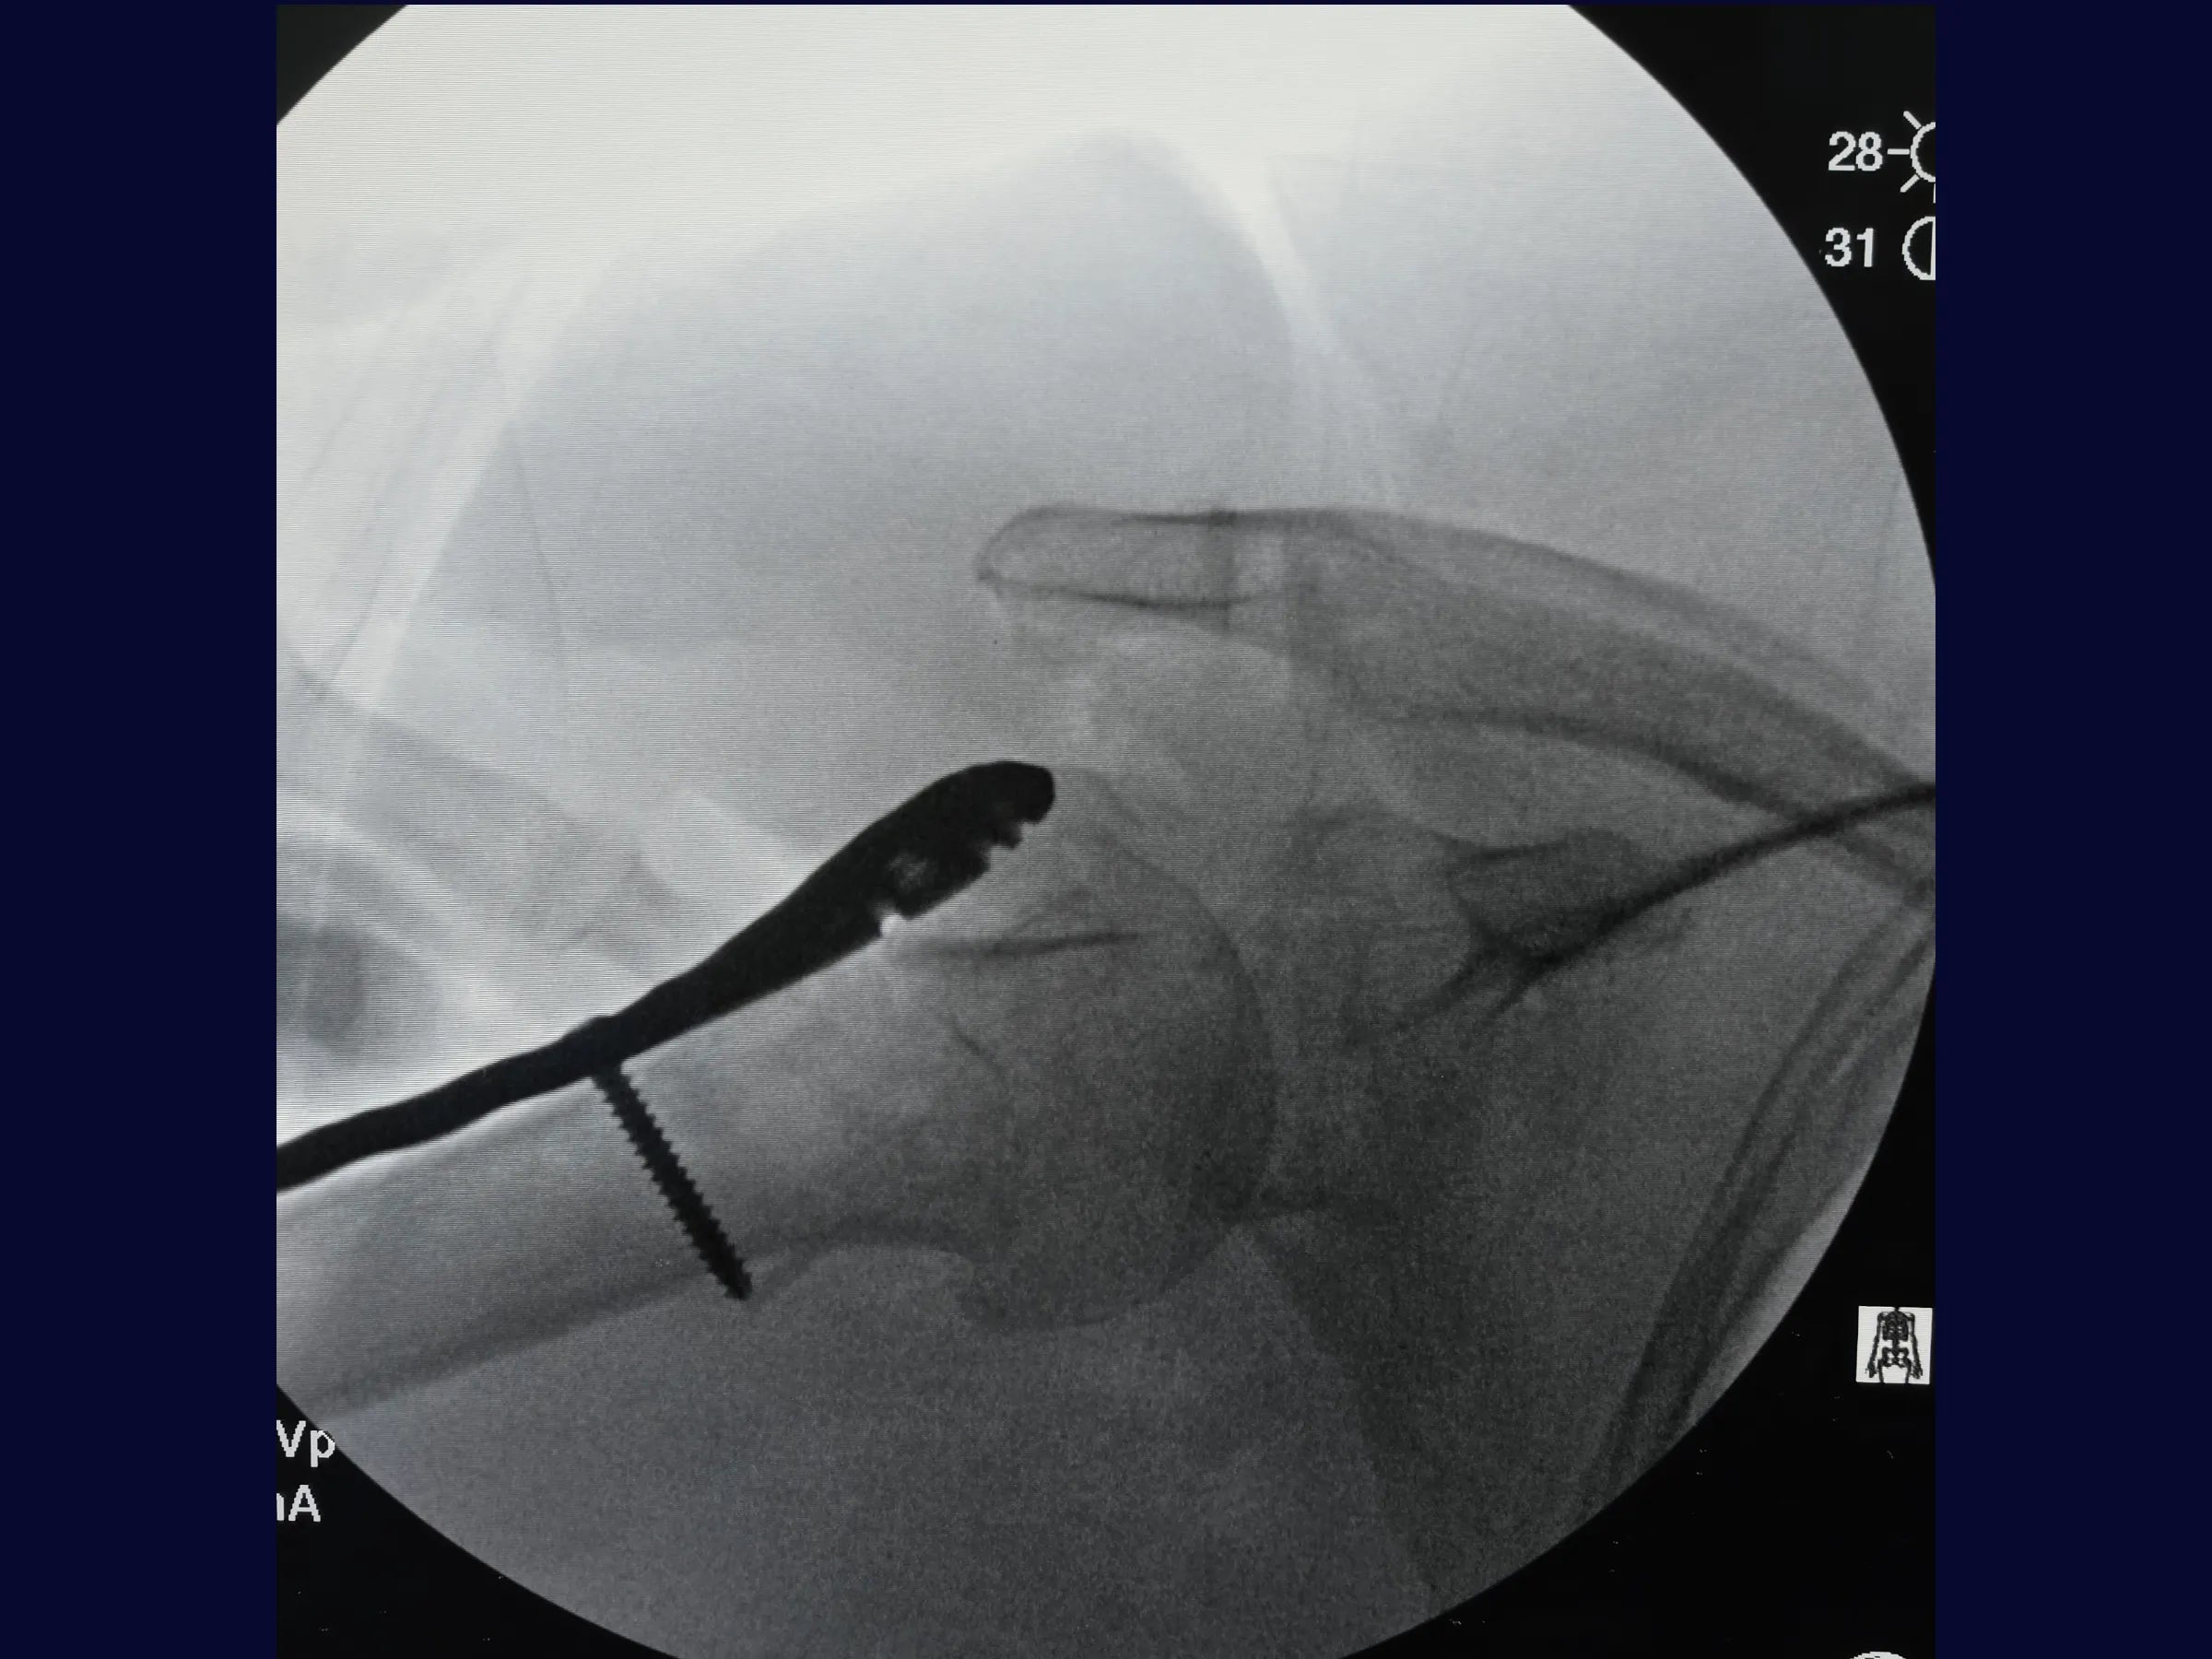

Este treinamento apresenta, passo a passo, a reconstrução do úmero proximal por via deltopeitoral, com ênfase na redução anatômica das tuberosidades e fixação estável com placa bloqueada, demonstrada sob perspectiva cirúrgica detalhada.

- Fixação com placa bloqueada e parafusos do calcar;

- Estabilidade Biomecânica: Fixação com parafusos do calcar e reforço com suturas de alta resistência.

- Controle Radiográfico e Ajustes Finais: Correção de cisalhamento e simetria com reposicionamento de parafusos.